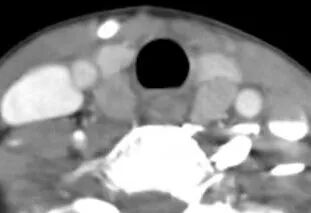

成都东篱医院 首例继发性甲旁亢手术 近期成都东篱医院在多学科协作(MDT)模式下,集结多学科技术力量(外一科、肾内科、超声科、麻醉科、病理科、检验科、放射科等),为一例继发性甲状旁腺功能亢进患者,成功实施我院首例“甲状旁腺全切除术+甲状旁腺自体移术”。 据悉,52岁的黄女士是一位尿毒症合并继发性甲状旁腺功能亢进患者。黄女士进行血液透析治疗已经11年,早在3年前就出现全身多关节疼痛、皮肤瘙痒,且血甲状旁腺激素(PTH)也在逐渐升高;虽长期服用药物治疗,但治疗效果有限。忍受病痛折磨的黄女士四处寻医,辗转来到成都东篱医院外一科,化验显示甲状旁腺素高达2693pg/ml,彩超检查发现甲状旁腺增生明显。 术前超声和CT增生甲状旁腺的表现 临床上对于继发性甲状旁腺功能亢进的治疗主要有药物治疗和手术治疗。外一科黄启荣主任介绍到:“当甲状旁腺进入结节性增生阶段后,常规的内科治疗大多无效,******的办法就是手术治疗。但甲状旁腺位于颈内深部,临近喉上神经、喉返神经、气管及食道等重要脏器,易损伤致严重并发症;加之尿毒症继发性甲旁亢患者身体情况较差,对手术及麻醉的耐受性差,围手术期管理非常困难,因而尽管目前急需手术治疗的继发性甲旁亢的尿毒症病人很多,但是因为手术风险高,难度大,开展该技术的医院较少。” 黄启荣主任组织全科认真研究分析了黄女士的病情,认为虽然困难重重,但手术是惟一的希望,决心利用“多学科联合诊疗”来寻求突破。外一科、肾内科、超声科、麻醉科、病理科、检验科、放射科等多个科室参与会诊、协调合作,共赴“战场”。 10月20日,为黄女士成功实施了“甲状旁腺全切除+左前臂甲状旁腺自体移植术”,手术过程非常顺利,甲状旁腺完整切除。术后甲状旁腺激素迅速恢复至正常水平(术前高达2693pg/ml,术后30分钟降至356pg/ml,术后第二天56pg/ml),未出现声音嘶哑、呛咳、喉头水肿等并发症,由甲旁亢引起的骨痛和瘙痒也明显缓解。因患者恢复良好,术后5天便顺利出院。 术中切除的4个甲状旁腺 待移植的甲状旁腺 该手术是我院成功开展的首例继发性甲旁亢手术,填补了我院在该治疗领域的空白,标志着我院在继发性甲状旁腺功能亢进治疗上取得了全新的突破!今后,我院继发性甲状旁腺功能亢进治疗将向MDT常态化开展,每位患者经MDT团队综合评估后量身定制手术方案,形成术前、术中、术后严密监测、精细化管理,将进一步提高中晚期继发性甲状旁腺功能亢进病人存活率及生活质量。